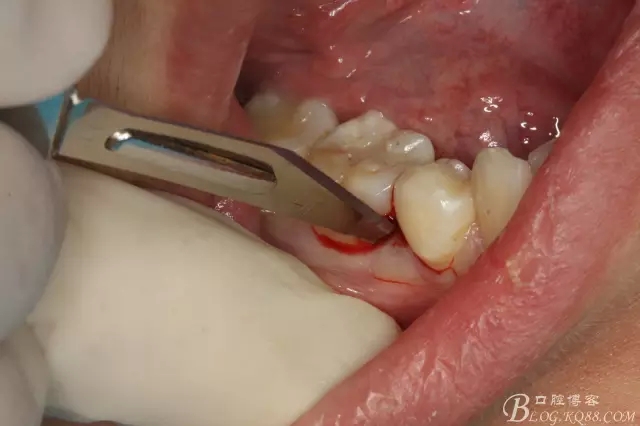

圖5.局部麻醉下、在44近中做垂直小切口,切口不要超過膜齦聯(lián)合。

圖6.齦溝內(nèi)水平切口

圖7.翻小瓣。暴露45牙根斷面